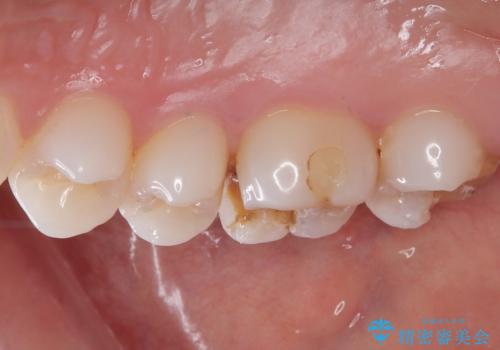

- 銀歯の詰め物が外れてしまったので、これを機にセラミックにやり替えたいと来院されれた患者様です。

虫歯になってしまっているところをしっかりと除去し、形を整えて、精度の高いシリコーンによる型どりを行いました。